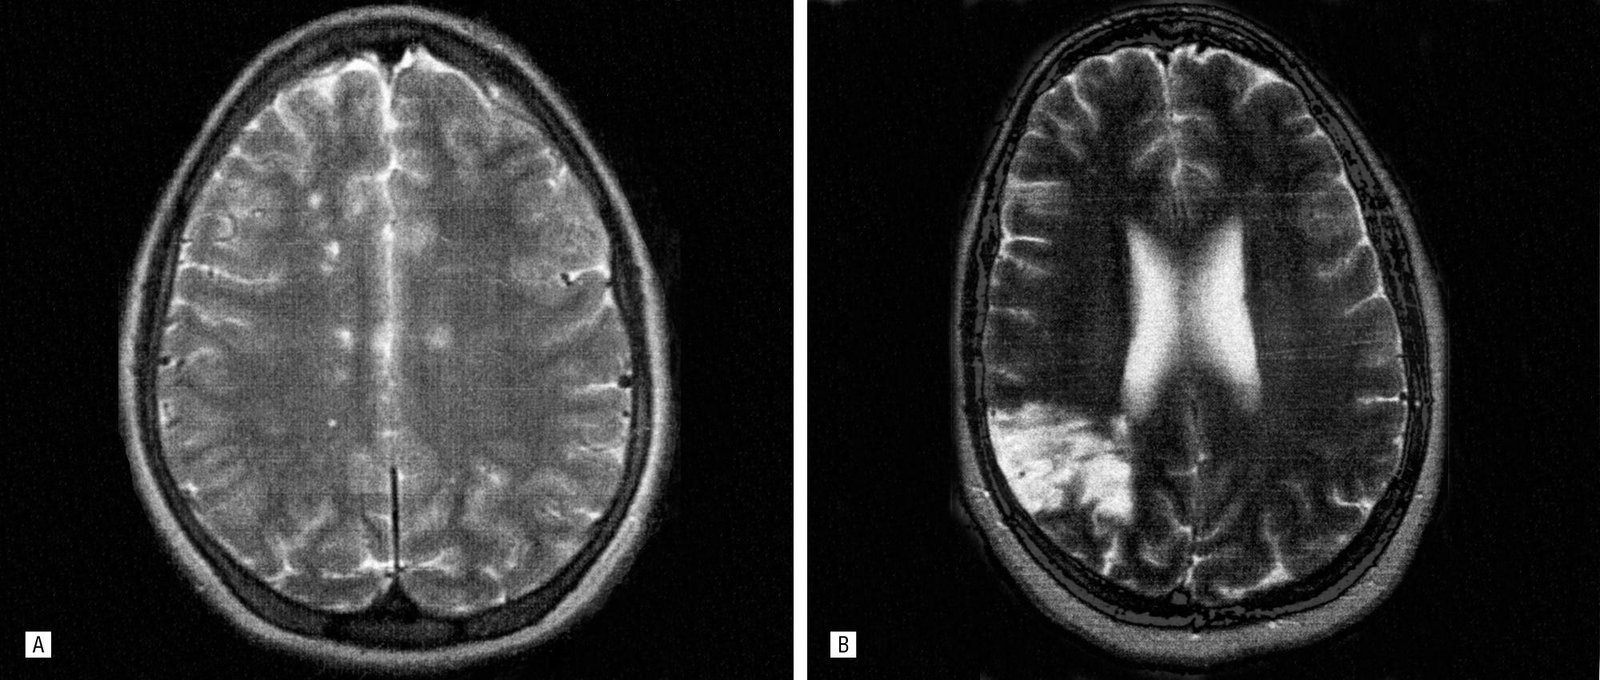

Як діагностують? Комп’ютерні технології приходять на допомогу: МРТ, КТ, електроенцефалографія.